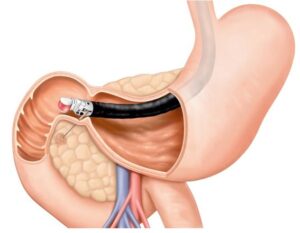

Pacientes que têm o objetivo de emagrecer, podem ter como alternativa a passagem de um balão intragástrico. A passagem do balão é realizada por endoscopia e o procedimento dura cerca de 20 a 30 minutos.

Passagem de Balão Intragástrico

1. O balão intragástrico é introduzido desinsuflado durante a endoscopia e colocado no estômago.

2. Um líquido azul (azul de metileno diluído em soro fisiológico) é colocado dentro do balão através de uma válvula. O volume varia entre 500-700 ml.

3. O aparelho de endoscopia é removido e o balão intragástrico pode ser deixado por um período de até 6 meses.